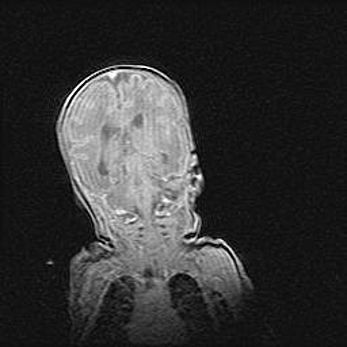

Лейкомаляция с кистозно-глиозной дегенерацией головного мозга.

Возраст: 2 месяца 25 дней

Вес: 6400 г

Окружность головы: 40 см

Срок гестации: 41 неделя

Лейкомаляцию относят к ишемически-гипоксическим повреждениям головного мозга, диагностируемым у новорожденных. При лейкомаляции в головном мозге обнаруживают очаги некроза, возникшие после тяжелой гипоксии и нарушения кровотока. В процессе морфогенеза очаги проходят три стадии: 1) развития некроза, 2) резорбции и 3) формирования глиозного рубца или кисты. Перивентрикулярная лейкомаляция (ПЛ) встречается примерно в 12% случаев среди новорожденных, обычно – у недоношенных детей, причем, частота ее зависит от массы, с которой младенец появился на свет. Наибольшее число малышей страдает лейкомаляцией, если масса при рождении 1500-2500 г.